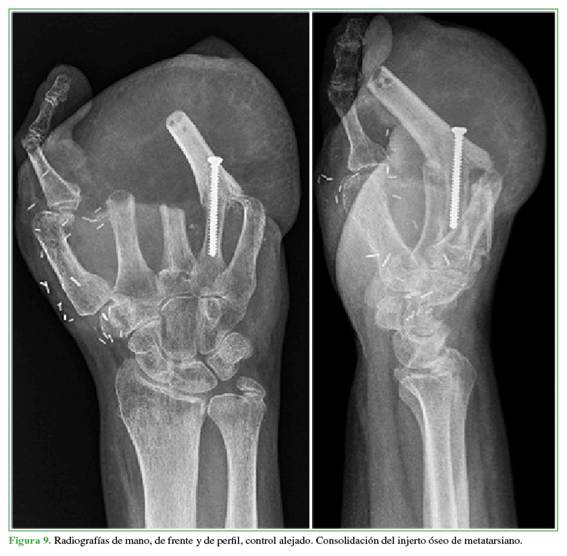

El injerto de metatarsiano tiene signos de consolidación tanto clínicos como radiológicos (Figura 9).

Por último, se abrió el colgajo inguinal por su cicatriz palmar longitudinal, con posterior exposición del cuarto metacarpiano y se colocó el injerto de segundo metatarsiano en ligera flexión, se fijó con un tornillo compresivo de 3,5 mm (Figura 6), y se logró una buena estabilidad. Se recubrió el injerto con el colgajo inguinal, así se obtuvo estructura para lograr pinza a futuro.